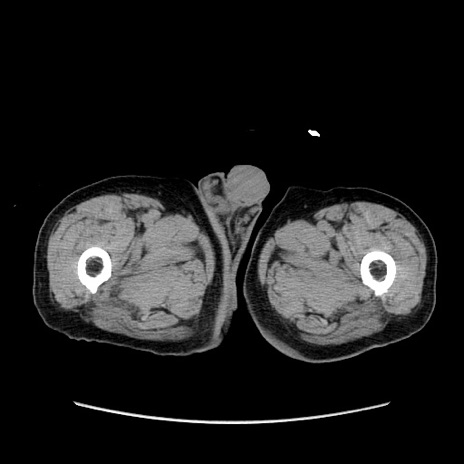

【症例】80歳代男性

【主訴】左側腹部痛、嘔吐

【現病歴】本日早朝より左腹部に痛みあり。昼頃嘔吐認めたため、救急要請。

【既往歴】直腸癌(Mile手術)、胆摘

【身体所見】意識清明、BT 35.9℃、BP 221/93mmHg、SpO2 97%(RA) 、腹部:左ストーマ周囲に限局性の腹部膨隆あり。 膨隆部自発痛・圧痛あり・軟。

【データ】WBC 7700、CRP 0.09